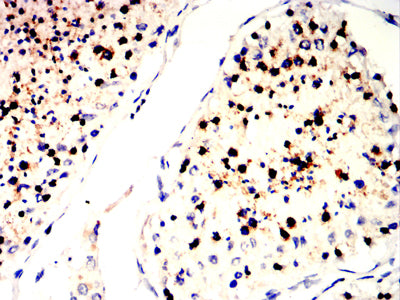

分类: 科研抗体货号: 32353别名: PARK8; RIPK7; ROCO2; AURA17; DARDARIN应用: IHC,FCM反应种属: Human